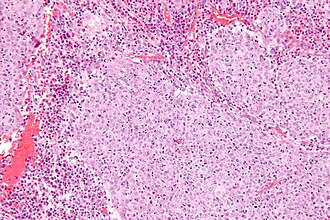

Glassy cell carcinoma. H&E stain. | |

| LM | epithelioid cells in sheets or cords with a round/oval nucleus, one or more prominent nucleoli, abundant finely vacuolated eosinophilic to amphophilic cytoplasm, distinct cell borders, inflammation - especially eosinophils |

- Epithelioid cells in sheets or cords with:

- Round/oval nucleus.

- One or more prominent nucleoli.

- Abundant finely vacuolated eosinophilic to amphophilic cytoplasm.

- Distinct cell borders.

- Inflammation - esp. eosinophils.[4]